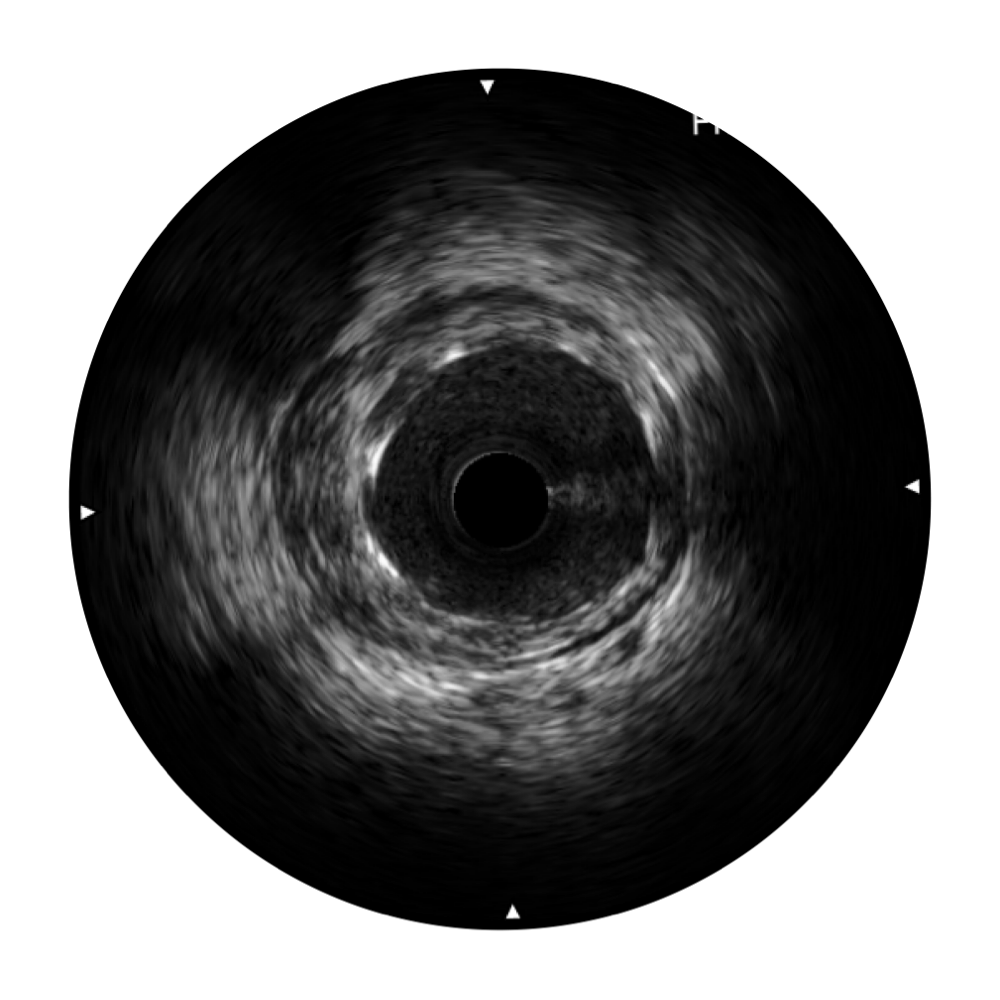

• 亚星官网宽频IVUS图像

• 传统IVUS图像

对比传统IVUS导管成像,亚星官网宽频IVUS图像的近场支架梁显影更细腻,远场中膜外血管仍清晰可辨,兼顾远中近,兼顾分辨力与穿透深度